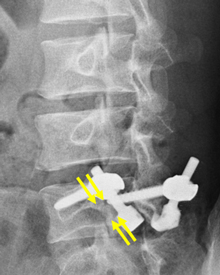

第4腰椎に前屈時に増強するすべりを認め不安定性を示しています。

MIS-TLIF(低侵襲腰椎後方椎体間固定術) 椎間板にケージと言われるスペーサーが挿入され、また経皮的に椎弓根スクリューの挿入とロッドの連結がなされ、第4腰椎のすべりが矯正され固定されています。